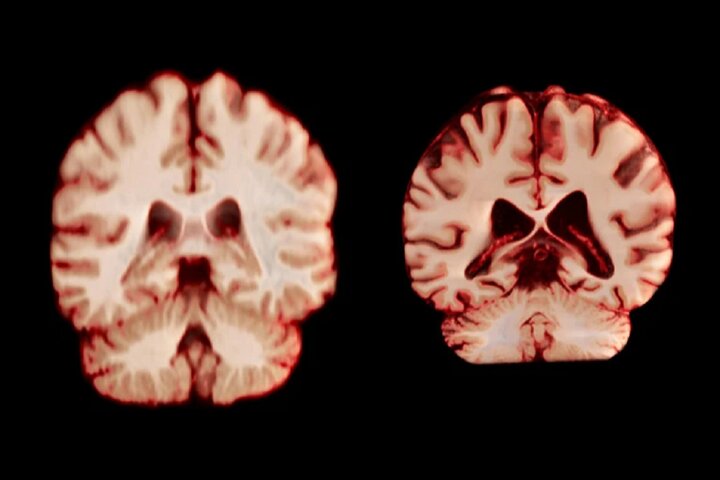

راوندال اضافه میکند که تحقیقات قبلی که تفاوتهای جنسیتی در پیری مغز را بررسی میکردند، نتایج متفاوتی را نشان دادهاند. چندین مطالعه نشان دادهاند که مردان در مقایسه با زنان، کاهش بیشتری در کل ماده خاکستری و اندازه هیپوکامپ را تجربه میکنند، در حالی که سایر تحقیقات، کاهش شدیدتر ماده خاکستری در زنان را گزارش کردهاند.

جدیدترین مطالعه شامل بیش از ۱۲ هزار و ۵۰۰ اسکن مغزی تصویربرداری تشدید مغناطیسی (MRI) از ۴۷۲۶ نفر بود که حداقل دو اسکن برای هر نفر، با فاصله متوسط سه سال انجام شده بود که به بیماری آلزایمر یا هرگونه اختلال شناختی مبتلا نبودند و به عنوان شرکتکننده کنترل در ۱۴ مجموعه داده بزرگتر قرار داشتند. محققان با بررسی عواملی از جمله ضخامت ماده خاکستری و اندازه نواحی مرتبط با بیماری آلزایمر، مانند هیپوکامپ که برای حافظه ضروری است، نحوه تغییر ساختار مغز افراد را در طول زمان مقایسه کردند.

به طور کلی، مردان در مقایسه با زنان، کاهش حجم بیشتری را در مناطق بیشتری از مغز تجربه کردند. به عنوان مثال، قشر پس مرکزی که مسئول پردازش احساسات لامسه، درد و دما و همچنین موقعیت و حرکات بدن است، در مردان سالانه ۲.۰ درصد و در زنان سالانه ۱.۲ درصد کاهش یافت.

ایمی برادتمن، محقق بالینی در حوزه سلامت شناختی در دانشگاه موناش در ملبورن استرالیا، میگوید اگر این تغییرات نقشی در ابتلا به بیماری آلزایمر داشتند، این مطالعه نشان میداد که زنان در نواحی مرتبط با این بیماری، مانند هیپوکامپ که در حافظه نقش دارند، کاهش بیشتری را تجربه میکنند.